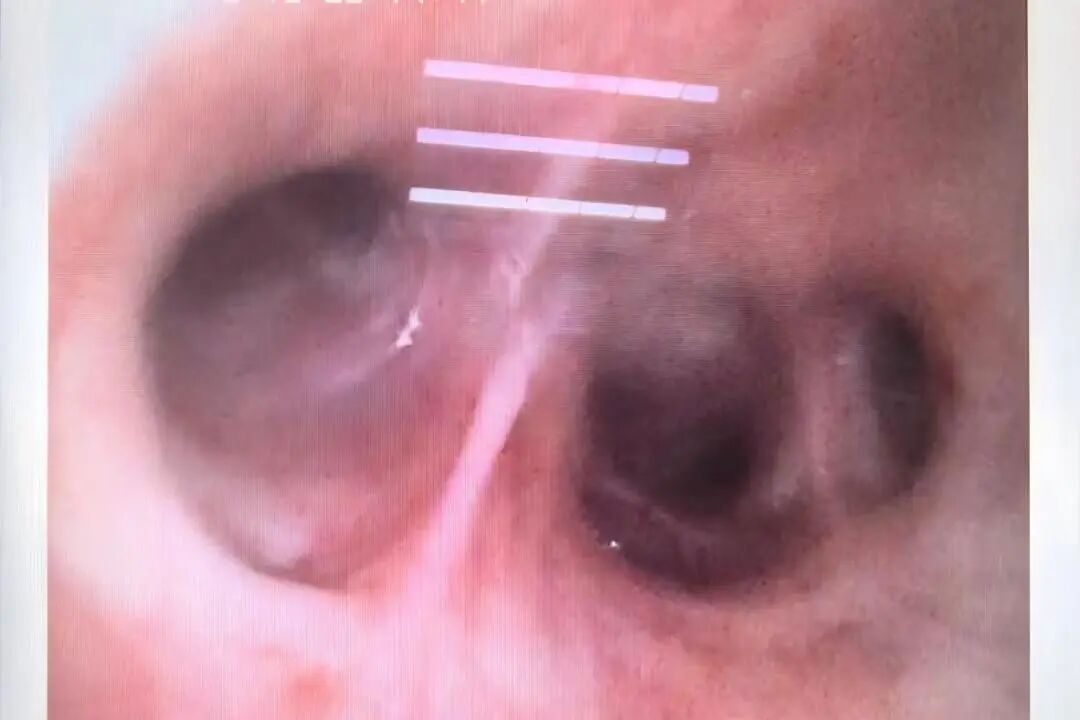

国庆假期期间,我院ICU成功救治一名罹患“罕见、危重、复杂”呼吸疾病的29岁患者。该患者因急性呼吸衰竭伴大咯血由外院紧急转入,入院时病情极为危重,胸部CT显示双肺弥漫性病灶,气管插管见大量血性液体,血氧饱和度一度降至50%以下。 入院时 CT提示双肺弥漫性病灶 近日复查 双肺渗出病灶明显吸收 入院时 肺部大量血性液体 住院期间 肺泡出血情况改善 接诊后,ICU团队迅速给予呼吸机支持、床旁支气管镜检查等救治措施,稳定患者生命体征。同时,医务部立即启动应急机制,组织呼吸与危重症医学科、肾脏风湿科、医学影像科、心血管内科、药学部等多学科专家会诊,国务院政府特殊津贴专家、呼吸与危重症医学科学科带头人廖江荣教授为患者进行床旁气管镜肺活检及支气管灌洗,诊断为弥漫性肺泡出血综合征(临床罕见、死亡率极高)合并急性呼吸窘迫综合征,为后续治疗提供了关键的循证依据。 ICU团队根据病情变化及时调整治疗措施,经过9天的精心治疗,患者生命体征保持平稳,肺泡出血情况逐步改善,肺部影像学表现明显好转,成功脱离了呼吸机支持,并转入普通病房继续治疗,现已好转出院。 专家提醒 弥漫性肺泡出血是以痰中带血、咯血、呼吸困难、进行性贫血和影像呈弥漫性肺泡浸润为特征的临床综合征。可由多种因素激发,基础疾病也多种多样,并且多数发病迅速,缺少特异性诊断方法,若不能早期诊断、及时治疗,则病死率很高。 若出现原因不明的急性呼吸困难、咳嗽、咯血等症状,特别是症状在短时间内迅速加重时,务必高度重视,应立即前往具备急救条件的医院就诊,争取早期诊断和治疗。 对于伴有自身免疫性疾病等相关基础疾病的患者,需定期随访,规范治疗,以预防严重并发症的发生。 贵州航天医院重症医学科专家简介 国务院政府特殊津贴专家 呼吸与危重症医学科 学科带头人 二级教授 硕士研究生导师 主任医师 学术任职: 亚洲冷冻治疗学会副主席 中国医药教育协会介入微创专业委员会呼吸分会副主任委员 中国防痨协会超声专业委员会副主任委员 中国抗癌协会肿瘤微创治疗专业委员会常务委员  中国防痨协会多学科诊疗专业委员会常务委员 中国医疗保健国际交流促进会结核病学分会常务委员 第一届中国人体健康科技促进会呼吸介入专业委员会常务委员 中国抗癌协会第一届肿瘤组织间植入治疗专业委员会常务委员 西部呼吸介入联盟副理事长 贵州省医学会呼吸病学分会第六届委员会副主任委员 贵州省中西医结合呼吸专业委员会副主任委员 贵州省医学会结核病分会常务委员 遵义市呼吸内科专业医疗质控中心主任委员 遵义市中西医结合学会理事长 专业擅长:  呼吸系统(肺)疑难病的诊断及危重病的抢救,呼吸系统(肺)感染性、疑难性疾病介入快速诊断(ROSE),尤其在肺癌、肺小结节早期诊断,肺癌微创综合靶向治疗,难治性、复治性、重症肺结核诊疗,硬质支气管下复杂性气道狭窄诊治,纤支镜介入治疗气道肿瘤、结核、气道狭窄(球囊扩张、支架植入、高频电刀、氩气刀、冷冻、灌洗、注药、微波消融),间质性肺疾病的诊疗上具有极高水平;带领团队勇于创新,在贵州省率先开展多项新技术、新疗法,如CT引导下及纤支镜下I125粒子植入及CT引导下微波、冷冻消融介入治疗肺癌等多项新技术,带动了贵州省肺部疾病的介入治疗水平提高。 刘东育 中共党员,重症医学科主任,主任医师 专业擅长:从事重症医学领域多年,擅长急危重症的各种抢救,有创呼吸机、无创呼吸机及CRRT的使用,对重症创伤及休克、急性重症胰腺炎、心脑血管疾病、各种急性中毒、多器官功能衰竭、重症肺炎及急性呼吸窘迫综合症等疾病的救治具有丰富的临床经验。 遵义市医学会重症医学分会第二届委员会常务委员,遵义市质量控制中心第一届重症医学质量控制中心委员会副主任,发表重症医学专业论文多篇,遵义市医学会第一届器官捐献与移植学分会常务委员。 赵洪伟 民建会员,重症医学科副主任,副主任医师 专业擅长:从事重症医学领域多年,擅长急危重症的各种抢救,有创呼吸机、CRRT的使用,对各种急性中毒、多器官功能衰竭、重症创伤及休克、心脑血管疾病、急性重症胰腺炎及急性呼吸窘迫综合症等疾病的救治具有丰富的临床经验。 贵州省重症医学委员会委员、遵义市重症医学会委员、遵义市医学会重症医学分会委员,贵州省第一批援沪医疗队队员,发表重症医学专业论文多篇。 王  磊 致公党党员,重症医学科副主任医师 专业擅长:从事重症医学多年,擅长急危重症的各种抢救,对急性重症胰腺炎、重症创伤及休克、急性呼吸窘迫综合症等疾病的救治、有创呼吸机的使用,CRRT对各种急性中毒、多器官功能衰竭、脓毒血症等疾病的救治具有丰富的临床经验。 贵州省重症医学委员会委员、遵义市重症医学分会委员、遵义市播州区方舱医院医疗队队员。 吴英武 中共党员,重症医学科副主任医师 专业擅长:擅长各种急危重症的抢救,对脓毒血症、重症创伤及休克、重症胰腺炎、急性呼吸窘迫综合症等疾病的救治及在重症超声对危重症治疗、抢救等方面具有丰富的临床经验。 贵州省第一批援鄂医疗队队员、贵州省重症医学委员会委员、遵义市医学会重症医学分会委员,发明专利3项、发表重症医学专业论文多篇。 贵州航天医院重症医学科简介 贵州航天医院重症医学科目前共有医护人员27人,其中副高级以上专家5人,开放床位16张,床单元配备医疗桥架和床旁监护系统,心电监护27台、动态血流监测仪23台、有创呼吸机19台、无创呼吸机5台、高流量呼吸机2台、转运呼吸机1台、血气分析仪1台、除颤仪1台、床旁透析机1台、纤支镜1台、无创血流动力学监测仪(USOM)1台、床旁B超机1台,降温毯1台、输液泵10台、微量注射泵74台、空气消毒机2台。 专科特色技术 心脏电转复及除颤术,气管插管术(经鼻气管插管术、经口气管插管术),气管切开术(经皮快速气管切开术、纤支镜引导下经皮快速气管切开术、超声定位纤支镜引导下经皮快速气管切开术),呼吸机的临床应用、心电、血压、脉搏、血氧饱和度监测技术、有创动态血压监测技术,有创动静脉置管术、锁骨下静脉穿刺技术、颈内静脉穿刺术、股静脉穿刺术、腋静脉穿刺置管术、血液净化临时血管通路的建立、鼻空肠置入术,跨肺压指导ARDS通气患者PEEP滴定应用,床旁超声测量视神经鞘直径评估颅内压,重症肺部超声评分在COPD患者中治疗效果应用,重症膈肌超声运动评估在机械通气患者撤机拔管中的应用,床旁超声测量下腔静脉呼吸变异指数在脓毒性休克机械通气患者容量反应性评估中应用价值。 诊疗范围 (一)急性、可逆、已经危及生命的脏器功能不全,经过严密监测和加强治疗短期内可能得到康复的患者。 (二)存在各种高危因素,具有潜在生命危险,经过严格监护和有效治疗可能减少死亡风险的患者。 (三)在慢性脏器功能不全的基础上,出现急性加重且已危及生命,经过严密监测和治疗可能恢复到原来状态的患者。 (四)其他适合在重症医学科进行严密监测和加强治疗的可逆性疾病患者 END